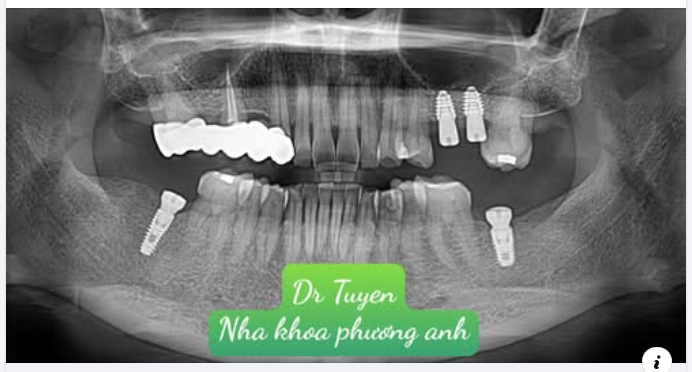

Ghép xương ổ răng được thực hiện sau khi mất răng hoặc nhổ răng được gọi là sự bảo tồn ổ răng